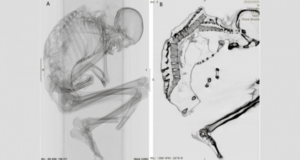

Ученые нашли мумию мужчины, умершего в результате несчастного случая на шахте более тысячи лет назад

Исследователи обнаружили перелом у основания позвоночника / фото Каталина Моралес и Франсиско ГарридоМумифицированные останки мужчины возрастом 1100 лет свидетельствуют о том, что он, вероятно, погиб в результате несчастного случая на древнем месторождении бирюзы в Чили. Об этом пишет Live Science. Согласно новому исследованию, опубликованном в Международном журнале остеоархеологии, обширные следы тупой травмы, обнаруженные на скелете мужчины, указывают на то, что он умер в ...